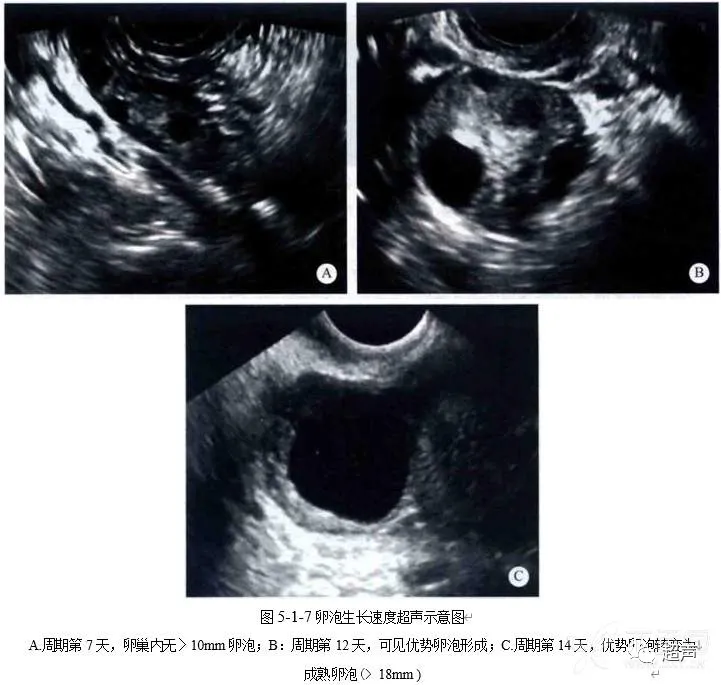

健康科普 | 好“孕”第一步——卵泡的超声监测